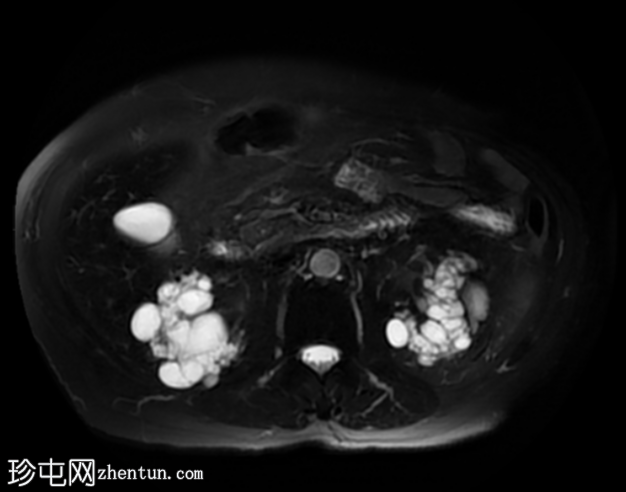

冠状位

T2加权像

双侧肾囊性疾病,可见多个肾囊肿,其中许多呈复杂性(出血性)囊肿,T1加权像呈高信号,T2加权像呈低信号。

左侧可见一较大的肾周血肿,与上极出血性囊肿相连,提示出血性囊肿破裂(Wunderlich综合征)。

未见肾脏软组织肿块。

轻度肝脾肿大,受检骨骼T2加权像呈弥漫性低信号,提示肾性骨营养不良。